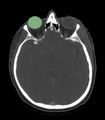

Segmentation of eye ball

- We are interested in segmenting the eye ball, lens, optic nerve, and the optic chiasm.

- We have the eye ball segmentation.